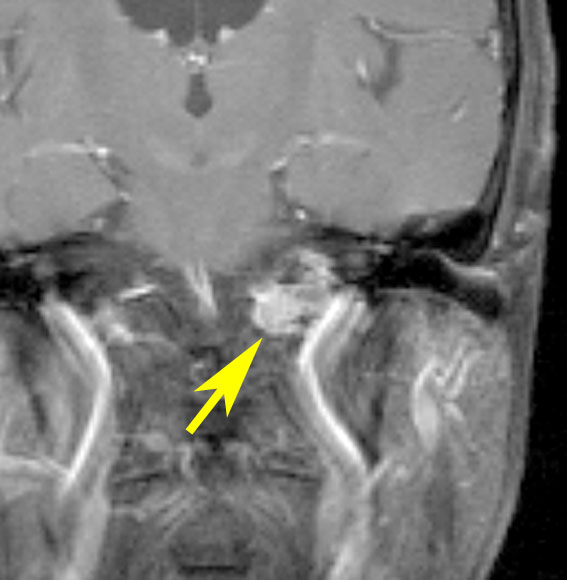

症例:小脳延髄角槽のもの,頸静脈孔へ少し入るもの

30歳くらいの女性に発生した無症状のものです。矢印のように拡大した頸静脈孔へ少し入っています。定位照射でもよかったかもしれませんが,若い女性なので手術しました。

脳槽部迷走神経根から発生したと考えて,外側後頭下開頭で摘出しましたが,予想外に延髄に近い部分の迷走神経から剥がせず,ほんの少し神経根の上に残しました。術後10年経ちますが腫瘍再燃はありません。聴神経腫瘍で顔面神経の上に薄く腫瘍を残すのと同じ考え方です。